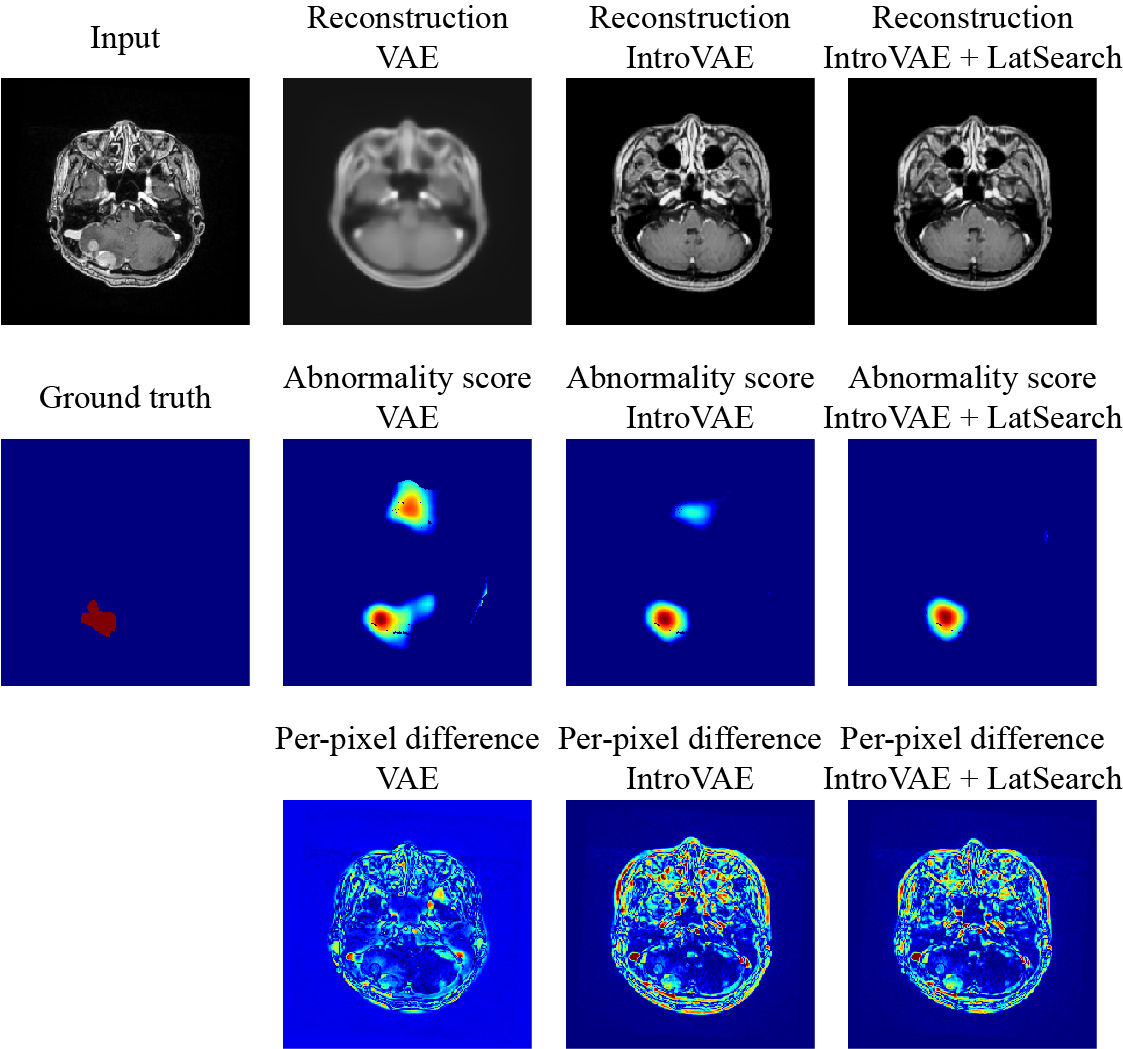

IV-C Distribution of Abnormality Scores

The previously proposed approaches that utilize image reconstruction networks trained solely on healthy images primarily evaluate pixel-wise residuals by calculating the L1 distances [6]. Therefore, we compared the per-pixel difference between the input and reconstructed images based on the abnormality score calculated using discriminative embeddings. As shown in Fig. 5, the L1 distance of the pixel intensities yielded a low signal-to-noise ratio. In contrast, a more meaningful distribution of abnormality scores corresponding to the presence of semantic objects (i.e., metastatic brain tumor shown by the red ground-truth label) was observed, where the tendency became the clearest when using IntroVAE+LatSearch.